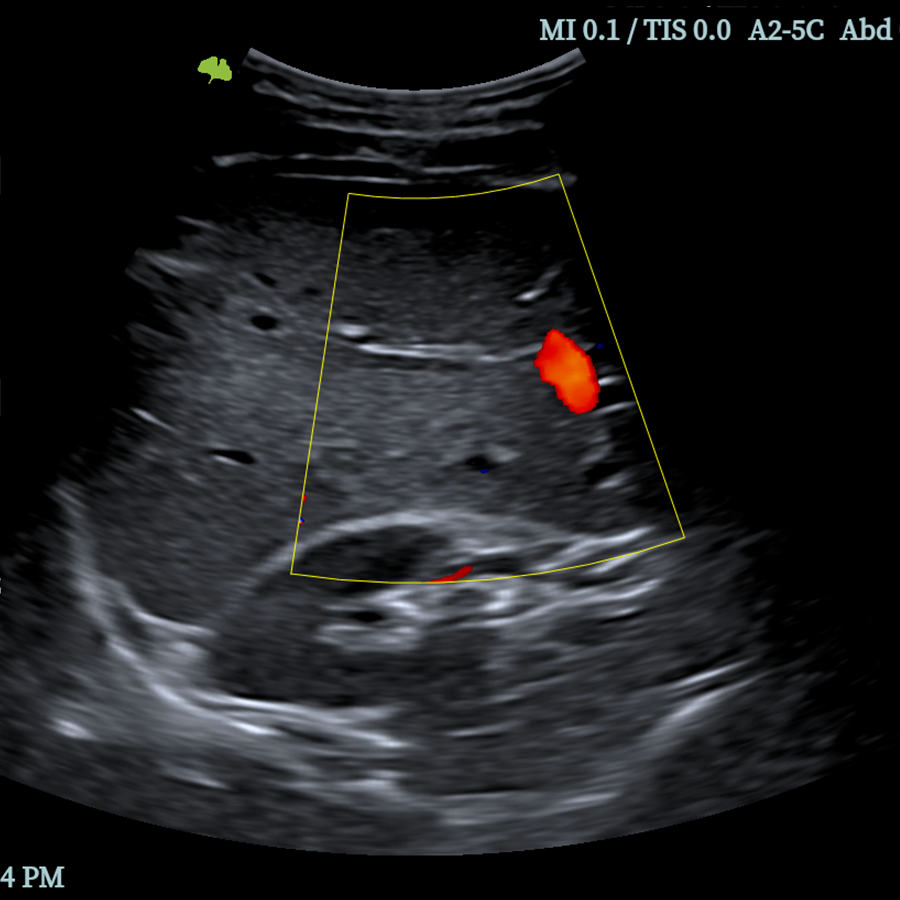

Doppler

- Modo M

- Modo CFM (Color)

- Modo DPI (Power)

- Modo PW (Pulsado)